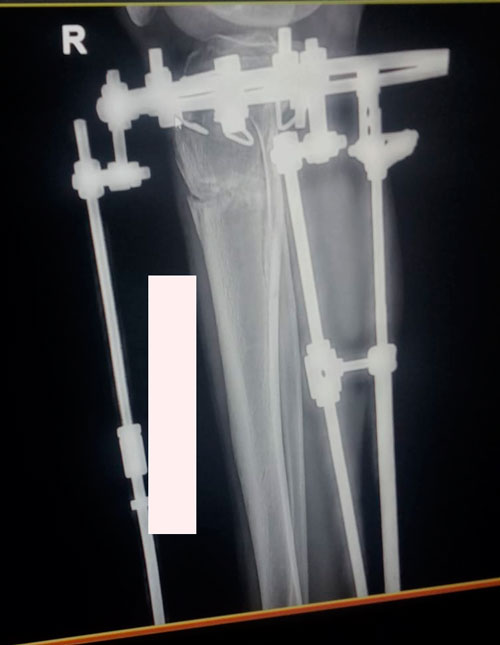

Рентген на 20 ый день после операции.

Девочки умницы! Много ходят, что способствует лучшему сращению!